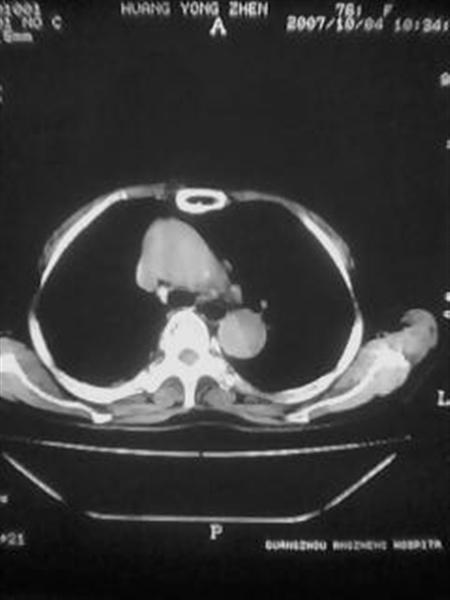

右下肺周围型肺癌伴双肺右侧叶间 胸膜及右肺门淋巴结转移

考虑:肺癌伴肺、胸膜 纵隔淋巴结转移可能性大!

怎么没有病史呢?支持:考虑肺癌,肺、胸膜转移可能性大.